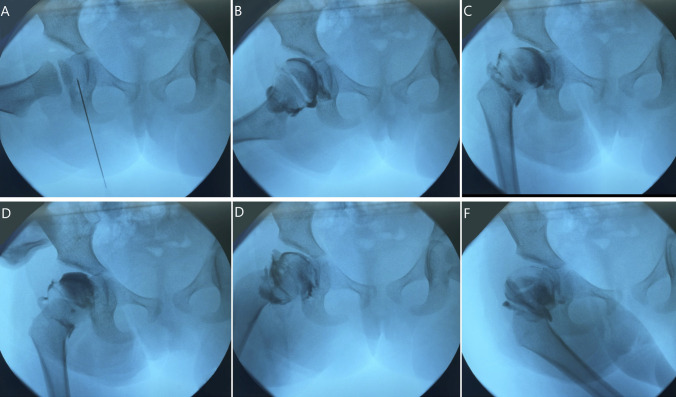

Methods: A prospective series was conducted in a single tertiary orthopaedic center. The procedure involved an initial examination of hip joint stability using intraoperative arthrography. The surgical procedure involved a small transverse incision distal and lateral to the anterior superior iliac spine, followed by a Dega osteotomy and bone allografting. Variables such as surgical time, blood loss, incision length, and acetabular index were measured.

Results: In healthy ambulatory patients, 16 osteotomies were performed on 12 patients with an average age of 32 months. The mean incision length was 2.3 cm, average blood loss was 17 mL, and mean surgical time was 21 minutes per side. Preoperative and postoperative acetabular indices averaged 40.3° and 18.6°, respectively. The mean follow-up period was 13 months. No complications were seen in this series.